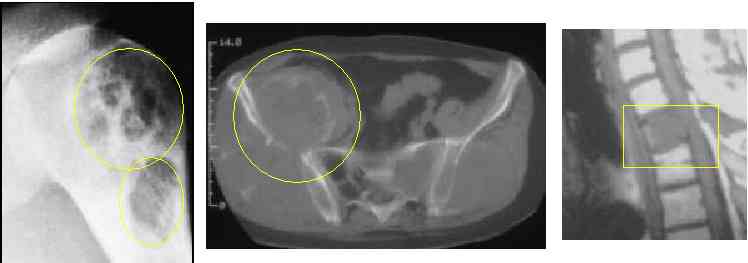

• a bone scan or CT are more sensitive than plain Xrays (see right hip met and see rib mets).Advanced spine mets can lead to spinal cord syndrome go here.

• some cancer make "black holes" or lytic mets (another lytic lesion), renal cell cancer causes lytic lesions (go here), and see CT showing diffusely mottled bone here and here